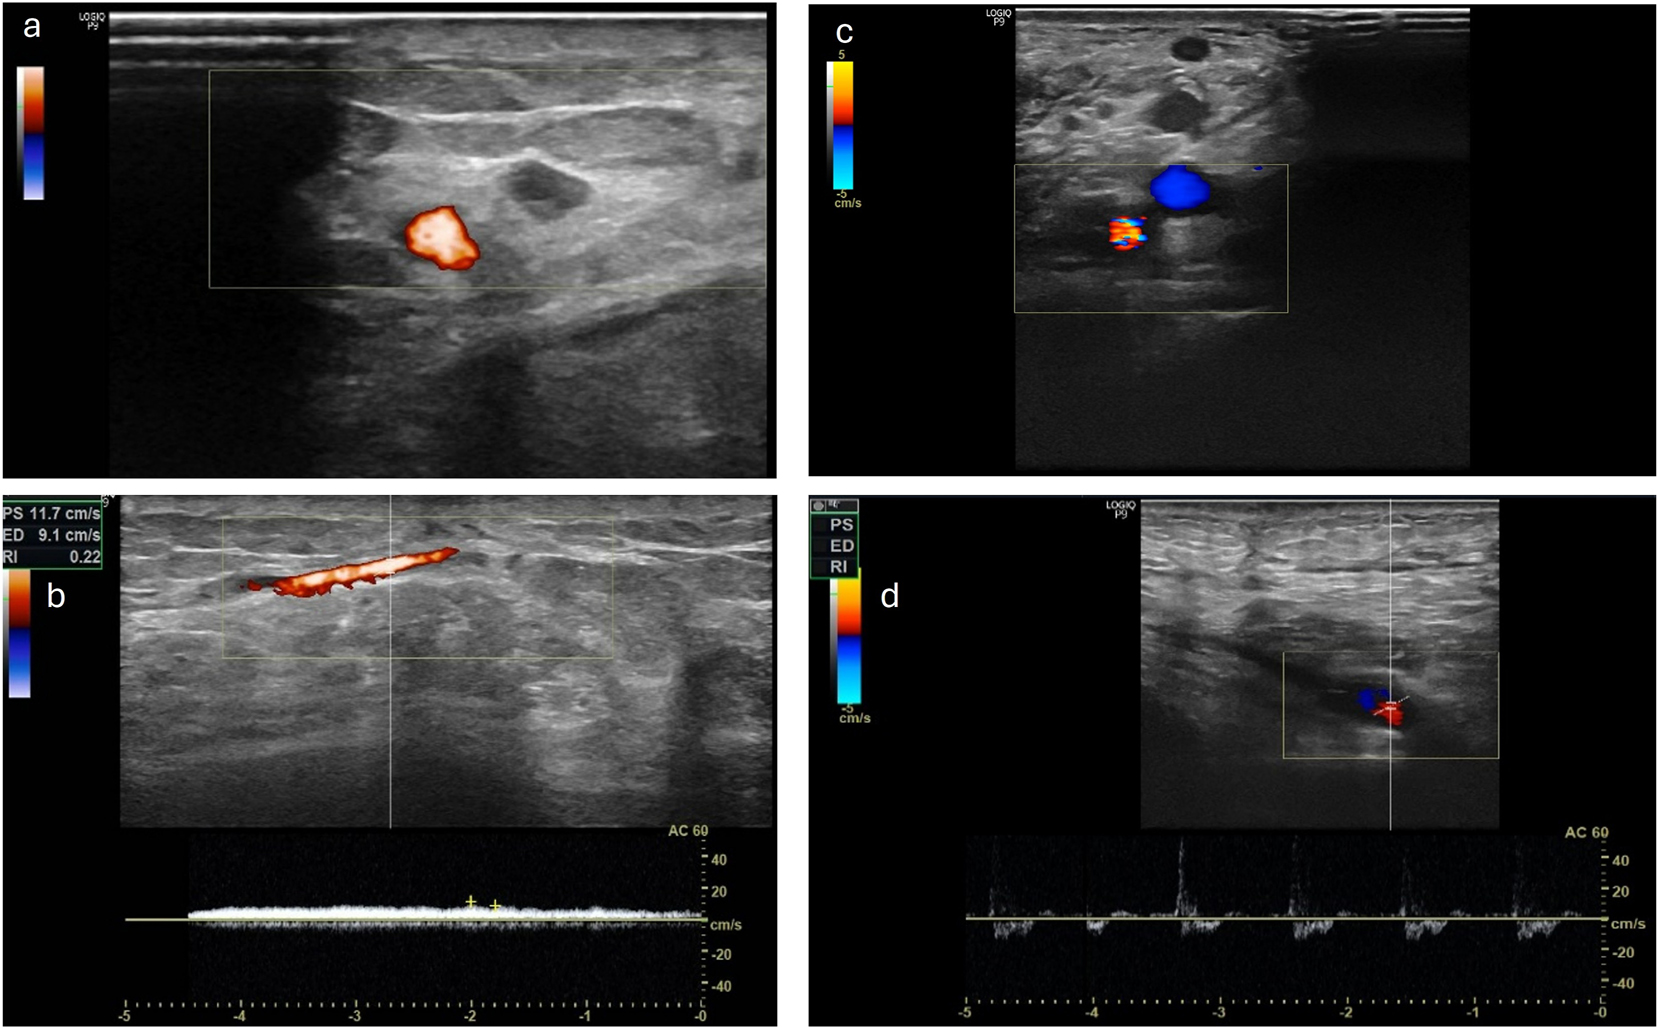

Further monitoring of the patients took place as part of the planned regular follow-ups. Here, the clinical assessment of the flap and the photographic documentation of the transplanted flap were carried out. This enabled the retrospective evaluation of the patients regarding successful transplantation and limb preservation. In four patients, an assessment of the pedicle using Doppler sonography could additionally be performed. Overall, the procedure shows a critical interval in the first month. In the further course, a stable flap situation is observed in the patients we evaluated. One patient died due to her underlying conditions after 621 days with the flap still in place. In one patient, there was an indirect flap loss after 923 days following amputation of the corresponding limb due to osteomyelitis of the heel, without any causal connection to the procedure we performed. Sonographically, an occluded pedicle was observed in two patients with a vital flap. In one patient, only the venous outflow could be demonstrated through the former loop. In one patient, open pedicle vessels were sonographically shown after 1,168 days (Figure 4). Regarding flap assessment, no significant differences were observed between the patients with patent, partially occluded or completely occluded loop.

Left side a) and b) the venous leg of the loop is still patent, with a venous flow signal in the CW Doppler ultrasound while arterial leg is occluded (patient VII) right side c) and d) the AV-loop is still patent and both legs are still perfused with an arterial flow signal in the CW Doppler (patient XII).